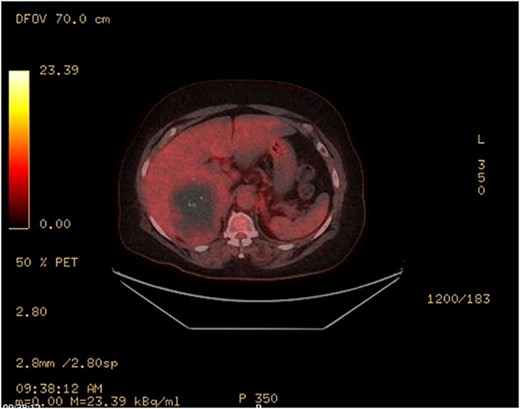

An MRI scan with gadolinium was arranged, demonstrating a complex right adrenal mass (9.8 × 8.2 × 8.1 cm). There was heterogeneous T1 and T2 signal with nodular peripheral enhancement and progressive filling-in (Fig. 2), suggestive of a giant adrenal haemangioma. A PET scan further demonstrated a photopenic mass with a mild peripheral rim of FDG accumulation (SUV max 3.4) (Fig. 3). The appearances did not suggest high-grade malignancy. A red cell scan did not identify progressive accumulation on delayed imaging, atypical for a haemangioma.

PET—large heterogenous complex right adrenal mass that measured up to 10 cm is largely photopenic with a mild peripheral rim of FDG accumulation (SUV max 3.4) at a level similar to adjacent physiologic hepatic activity.